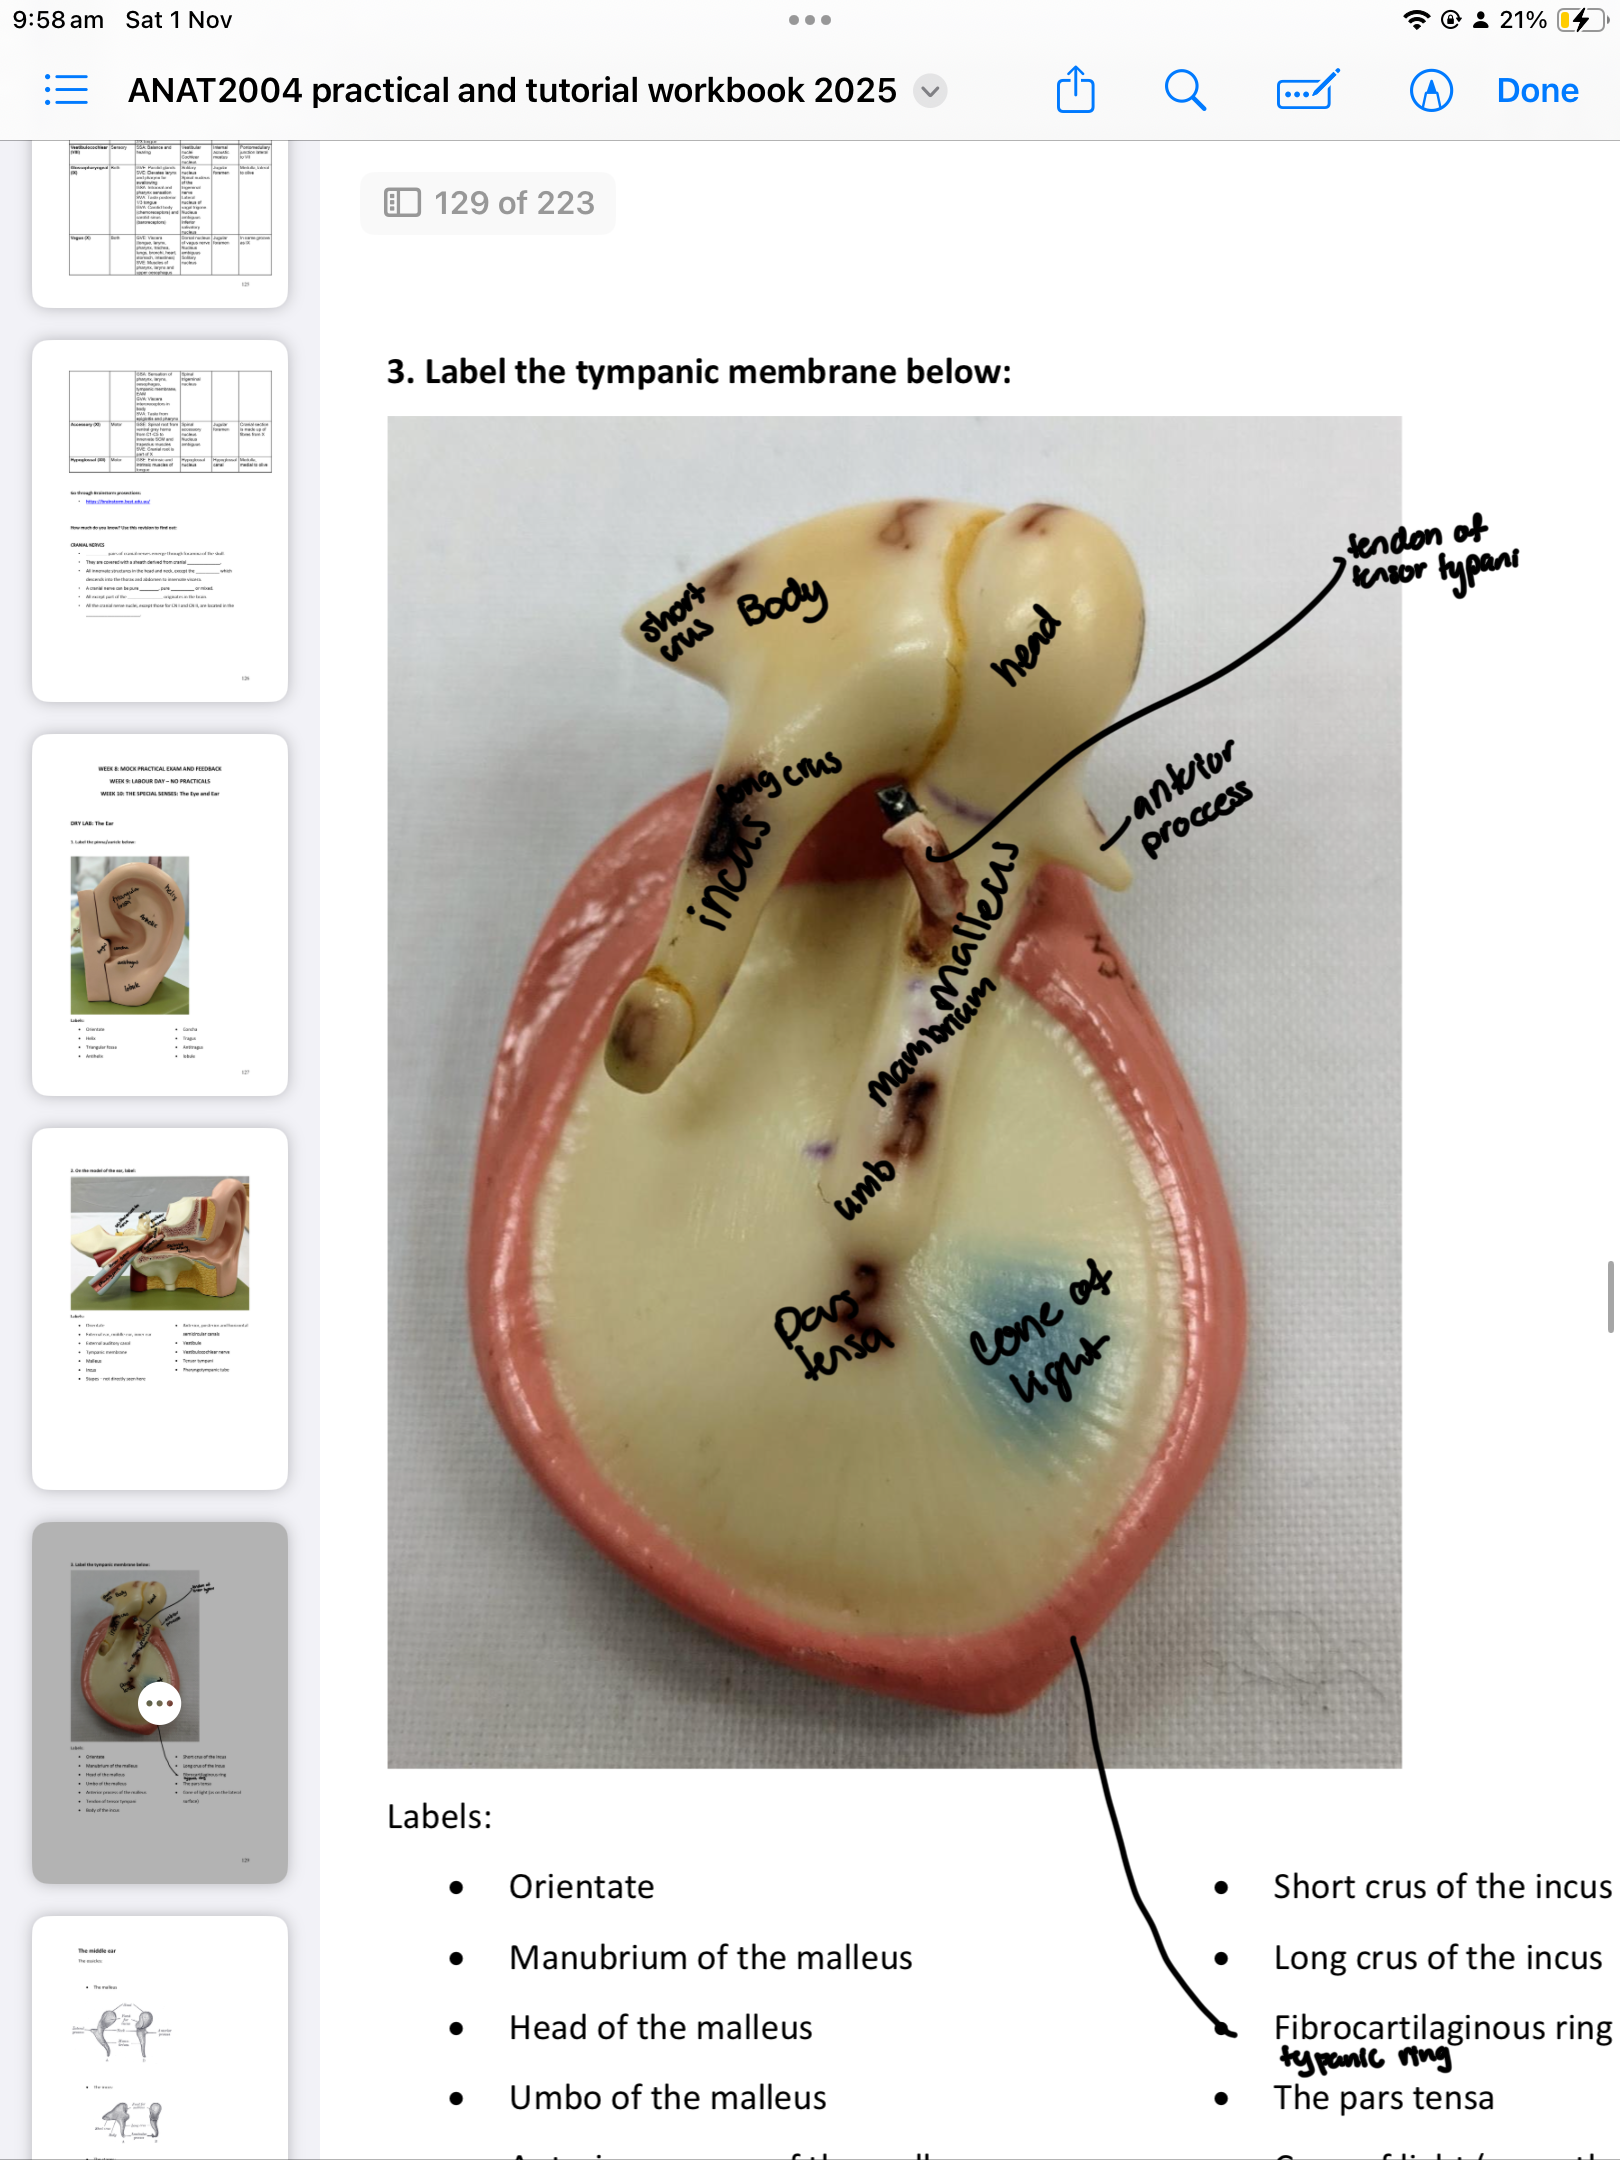

Cone of light

Manubrium of the malleus

Head of the malleus

Umbo of the malleus

Anterior process of the malleus

Tendon of tensor tympani

Body of the incus

Short crus of the incus

Long crus of the incus

Fibrocartilaginous ring

The pars tensa